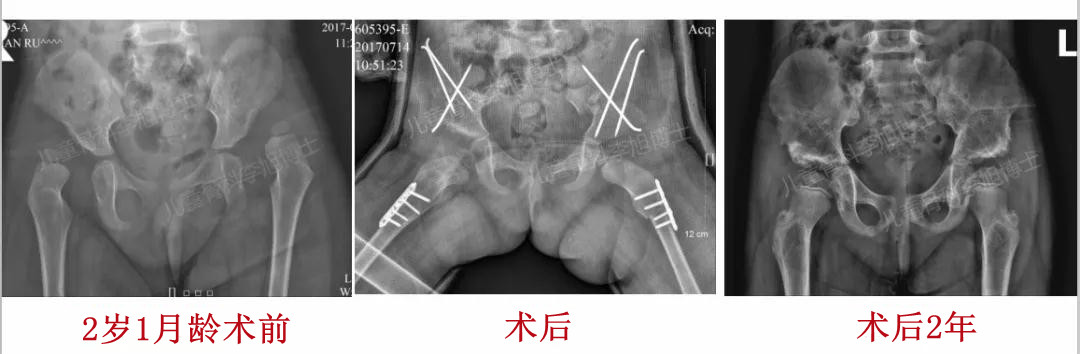

2、18月龄以上的孩子,通常建议开放复位,因为即使闭合复位成功了,后期发生残留畸形而再次截骨的手术风险都很大!

3、18月龄以内的孩子,应该首先尝试闭合复位,推荐在复位之前先进行悬吊牵引!如果初次闭合失败,那么再次去争取闭合的成功可能性极低,应该当机立断选择切开!切开不受年龄的限制,低龄不是切开的禁忌!!